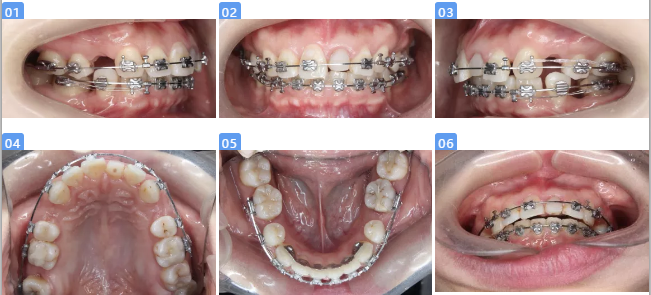

第一阶段:基础治疗

—OHI

—21根管治疗

—17、35、45残根拔除

—龋坏牙齿充填

—牙周治疗前后,牙周大表显示牙龈探诊出血阳性位点明显减少

第二阶段:正畸修复联合治疗

—粘接矫治器,合向牵引21

—上颌拔除14、24,右上采用中等支抗内收关闭间隙,左上强支抗

—下颌弱支抗关闭间隙(前牙3D打印舌侧夹板)

—21树脂冠确定近远中径,粘接矫治器对其转矩精细调整

—21颊腭侧牙周修整